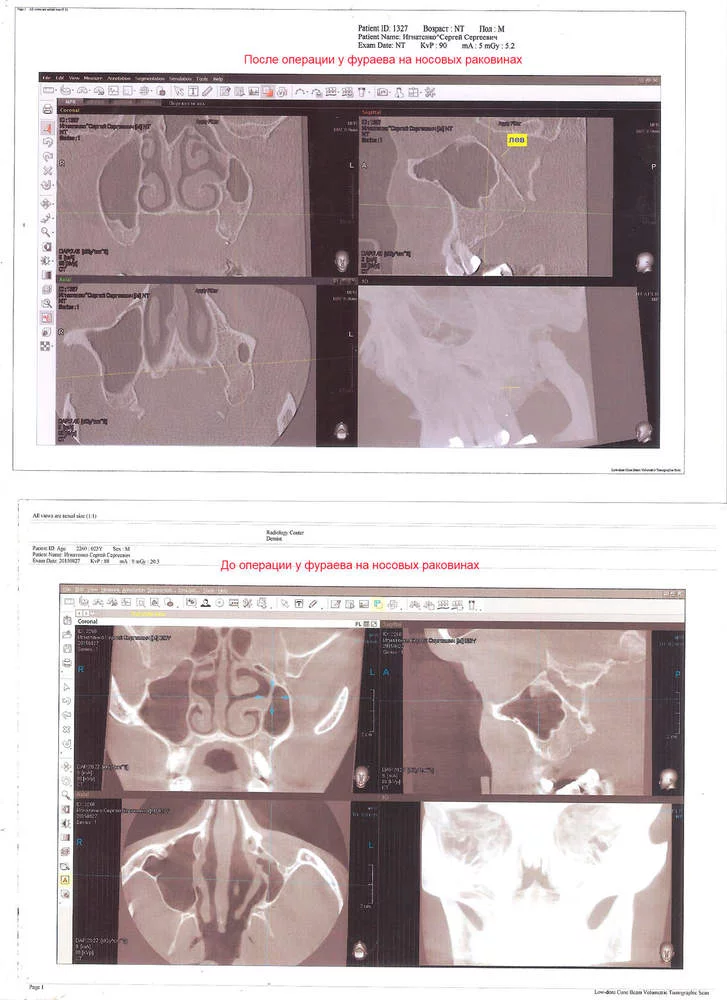

Случайно нашел в интернете отзывы о военном госпитале, что фураев делает на перегородках весьма хорошо операции в начале 2015 пошел к нему с томограмой, он удивился что в алексе меня недооперировали. Повезло, он искривление перегородки полностью убрал, стало чуть лучше дышать, но проблем ас раковинами оставалась. Через пол года я ему решил позвонить и договориться о консультации, но где то на протяжении четырёх месяцев как не позвоню он или в отпуске или на больничном, словно бред какой-то. Причем он говорил что вместе с перегородкой и с раковинами разберется.

В начале 2017 зимой пошел к нему томограммой он говорит нужно раковины подрезать концы и объём убирать чтобы легче дышать было. Прооперировал дышать стало немного лучше. Пришел через две недели говорю вроде поджило но дышать не намного лучше, уши болят также и только капли помогают отёк убирать. Хотя до этого много месяцев не капал, но ушную боль из-за носа тяжело терпеть и начинал вновь капать.

На снимке видно, что стоит отечь левой раковине хоть чуть чуть как дыхание перекрывается.